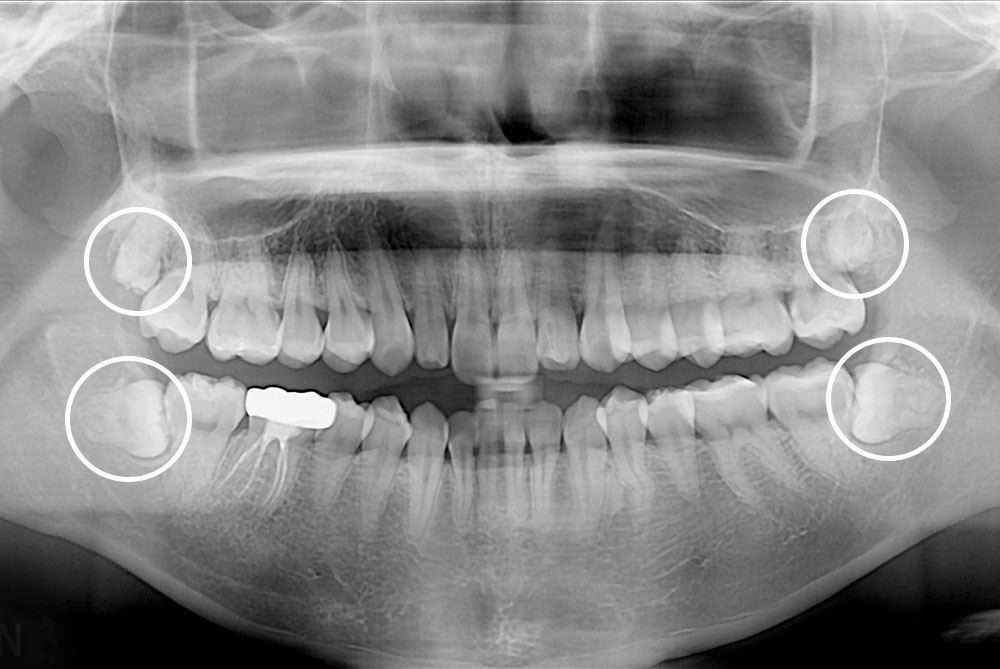

[사랑니] 매복 사랑니 발치

치료전 : 2018-10-16